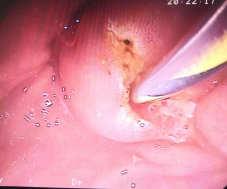

十二指肠乳头切开,脓性胆汁喷涌而出……

(EST术,即十二指肠乳头切开术) (十二指肠乳头切开后见脓性胆汁喷涌而出)